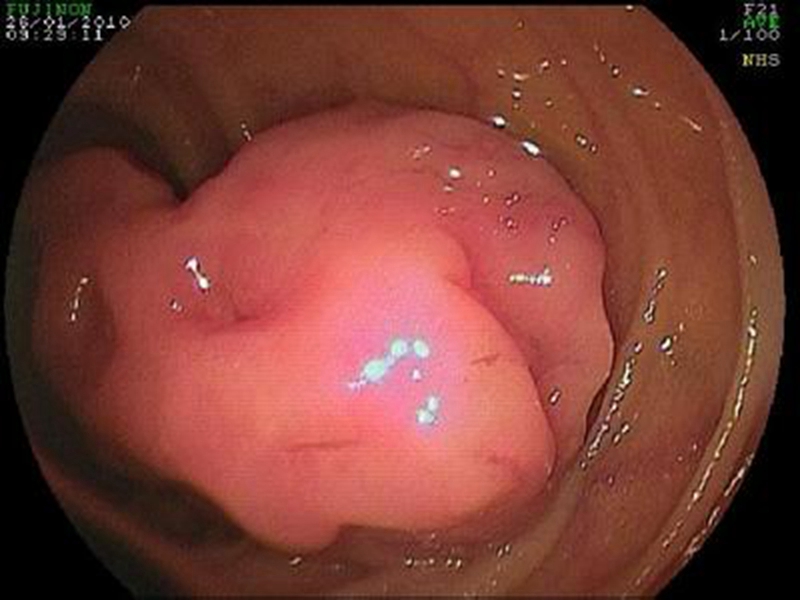

腸腫瘤圖片

腫瘤腸腫瘤細胞圖

腫瘤腸腫瘤真實

腫瘤腸腫瘤病變真

腫瘤腸腫瘤切除術

直腸腫瘤的報告單

直腸腫瘤惡性腸鏡

直腸腫瘤

直腸腫瘤早期

直腸腫瘤 良性